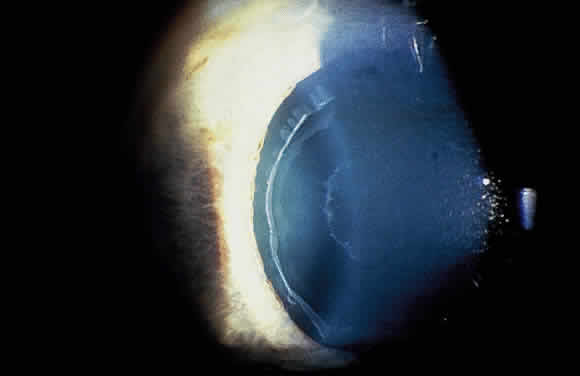

Lens

Deposition of exfoliative material on the anterior lens surface is the most commonly recognized feature of XFS and usually is best appreciated after pupillary dilation.43 A bull's-eye pattern generally is seen in which a translucent central zone and a granular peripheral zone of deposition are separated by an intermediate clear zone (Fig. 1). The translucent central zone of exfoliative material varies in diameter and may exhibit curled edges. In approximately 20% of patients with exfoliation, the central zone may be absent.38 The intermediate clear zone presumably results from lens contact with movement of the iris. The granular peripheral zone, which may be subtle but invariably is present in XFS, generally exhibits a well-delineated inner border and often shows numerous radial striations (Fig. 2). Occasionally, a bridge of exfoliative material may cross the clear zone to join the central zone and the granular peripheral zone.38,44

Fig. 1. Typical bull's-eye pattern of exfoliation on lens surface showing separation of central and peripheral zones of deposition by intermediate clear zone.

Fig. 2. Granular peripheral zone with well-defined inner border and numerous radial striations.